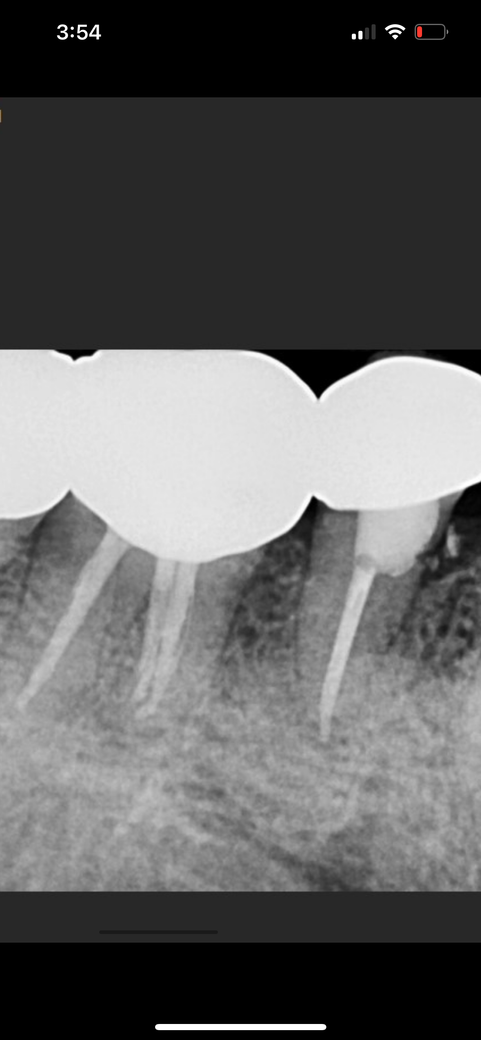

엑스레이좀 봐주세요! 치아가 아파요

엑스레이상 왼쪽 아래부분이 뜨거운걸 먹었을때

애리는 느낌이 나요.

저작 통증은 없구 대신 뜨거운 국밥같은걸 씹을땐

5초정도 아프고 말아요.

이미 신경치료15회와 + 다른이 신경치료+ 크라운 한 세곳중 한곳이 아픈듯해요.

병원 3군데선 염증 안보인다하고 한곳은 왼쪽 아래 소구치에서 약간 염증이 보이나 신경치료 완료한지 아직 2달밖에 안된거라 지켜봐야 한다고 하더라구요..

그러면서 ...왼쪽 윗부분 인레이도 뭔가 애메하다는듯이 말을 흐리셨는데 충치나 염증이 보이나요~?

• 1번 째 사진

1. 신경치료된 치아는 보통 찬 것에는 거의 증상이 없고 간혹 염증이 아직 있거나, 잔존신경이 있으면 뜨거운 것에 민감한 반응을 보이기도 합니다.

2. 이런 경우 재신경치료가 필요합니다.

3. 현재로서는 신경치료를 안하고 씌운 마지막 큰 어금니에 대해 추가검사를 해보면 좋을 것 같습니다.

4. 엑스레이상 왼쪽 위 작은 어금니 인레이 (#15)의 경우 인레이 보철물 하방 검은 색이 하방 우식일 수도 있고 엑스레이 상 왜곡일 수도 있습니다. 증상이 있다면 인레이 뜯고 내부 체크해봐야 합니다.